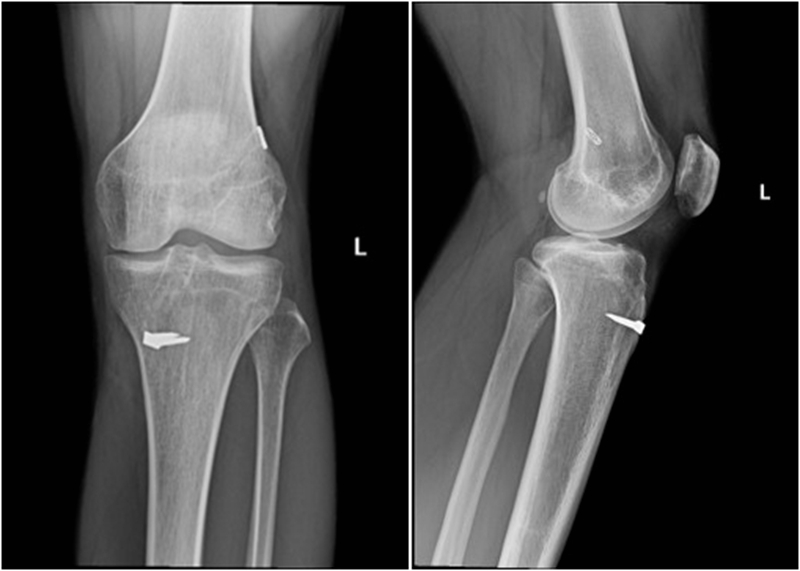

典型病例,张X,男,18岁,因扭伤致左膝关节疼痛伴活动受限1月余入院。

诊断:1.左膝前交叉韧带损伤;2.左膝外侧半月板损伤合并囊肿。

手术方案:左膝关节镜下清理、滑膜切除、外侧半月板部分切除成形、前交叉韧带重建术。

术前X线

术前MRI